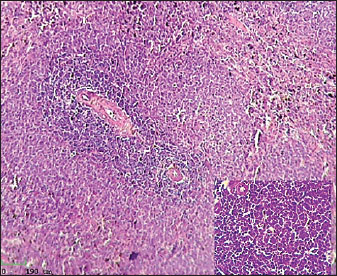

Histological analysis of spleen

Histological examination of the splenic tissue of rats treated with L-arginine showed notable pathological alterations. These included: Congestion of blood vessels within both the red and white pulp and lymphoid hyperplasia in the white pulp, indicating increased proliferation of lymphoid cells, suggestive of immune stimulation or chronic inflammation (Fig. 4). In contrast, the spleen from control male rats exhibited normal histological architecture. The white pulp and red pulp regions were clearly distinguishable. Central arteries and blood vessels appeared unremarkable, and no signs of congestion, inflammation, or hyperplasia were observed. The lymphoid follicles within the white pulp were of normal size and density (Fig. 3)

Fig. 3. Histological section of male rat spleen of control group, stained with Hematoxylin and Eosin (H&E), showing villus structure at 10x magnification using light microscopy.

Fig. 4. Histological section of male rat spleen treated with L-arginine, stained with Hematoxylin and Eosin (H&E), showing villus structure at 10x magnification using light microscopy.